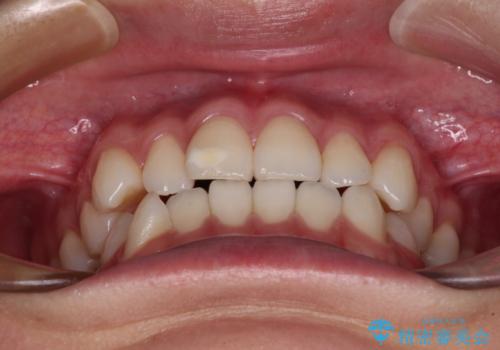

- 前歯のデコボコと奥歯の咬み合わせを気にして来院された患者様です。

右側の奥歯は、上が外側に転位した鋏状咬合を呈しており、前歯のデコボコ改善と並行して咬み合わせを改善していく必要がありました。